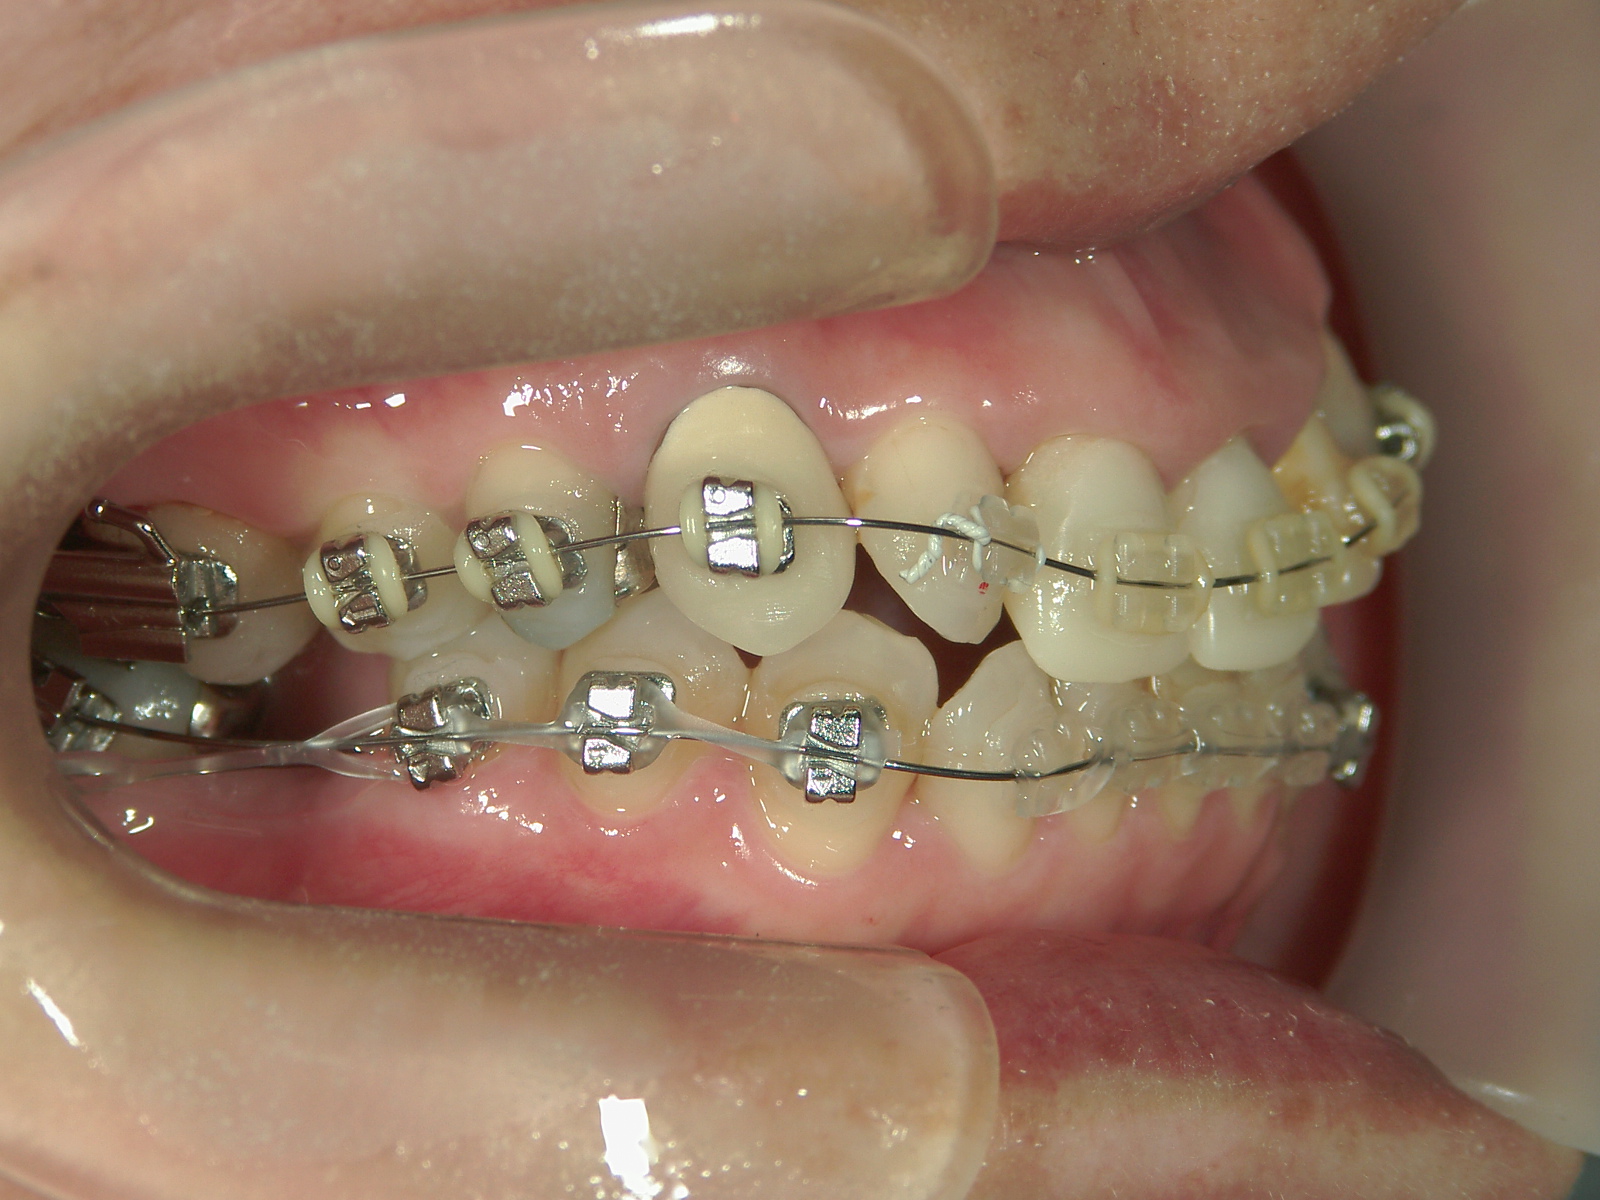

抜歯欠損症例(7)右下大臼歯 欠損・左下大臼歯 抜歯

主訴: 前歯揃えて引っ込めたい

右下 第一大臼歯 欠損。

右上 親不知1本、左下 第一大臼歯1本を抜歯。

ミニインプラント併用。

㊤前歯2本冠せ物をセラミックへ変更。